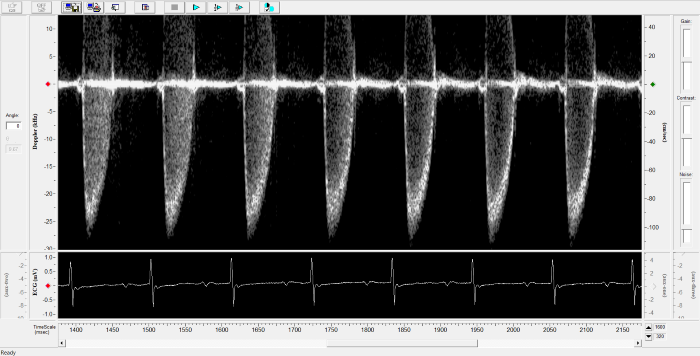

Imaging gallery - Doppler Flow Velocity System

Pulmonary Flow. Image Credit: Scintica Instrumentation Inc.